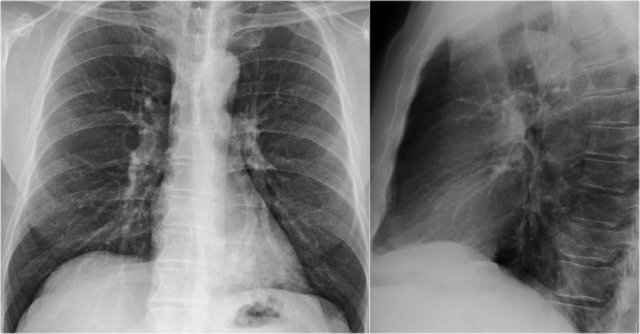

Another common cause of displacement of the azygoesophageal line is subcarinal lymphadenopathy.

Notice the displacement of the upper part of the azygoesophageal line on the chest x-ray in the area below the carina.

This is the result of massive lymphadenopathy in the subcarinal region (station 7).

There are also nodes on the right of the trachea displacing the right paratracheal line.

On the PET we can appreciate the massive lymphadenopathy far better than on the CXR.

There are also lymphomas in the neck.

this is an important finding, since these nodes are accessible for biopsy.

Continue with images of CT and ultrasound.

Here we see a CT-image.

The azygoesophageal recess is displaced by lymph nodes that compress the left atrium.

The final diagnosis of small cel lungcancer was made through a biopsy of a lymphnode in the neck.